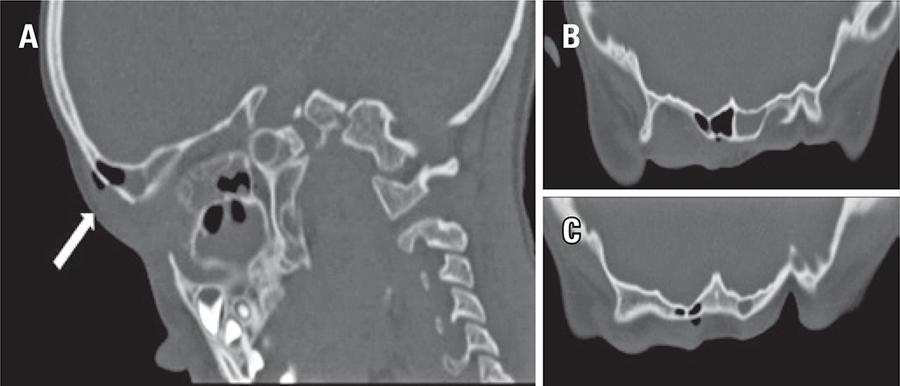

Criança de 5 anos de idade, sexo masculino, com antecedentes de fratura do seio frontal há 2 anos, tratada de maneira conservadora e, atualmente, sem seguimento por cirurgia. Apresentou-se à admissão com quadro febril agudo, edema marcado da pálpebra e região supraciliar direitas, acompanhados de movimento ocular doloroso homolateral. O exame físico não revelou outras alterações, excluindo-se o comprometimento neurológico. Os exames laboratoriais mostraram aumento dos marcadores de inflamação. Para estadiar a extensão da inflamação e excluir as complicações intracraniais, realizou-se tomografia computadorizada do crânio e órbitas, que revelou edema frontal e periorbitário à direita, estendendo-se à área pós-septal, sem envolvimento do nervo ótico. Foram também observados enfisema subcutâneo ao redor de ruptura, na continuidade da parede anterior do seio frontal, e um processo de pansinusite aguda, com níveis hidroaéreos nos seios maxilares, etmoidais, esfenoidais e frontais; não foi notada formação de abcesso. Admitiu-se o diagnóstico de celulite orbitária e enfisema subcutâneo facial devido à pansinusite. O enfisema subcutâneo facial é habitualmente relatado como uma complicação aguda da fratura óssea.(–) No entanto, neste caso, apresentou-se como uma complicação tardia, provavelmente desencadeada pelo processo agudo de sinusopatia frontal, o que constitui complicação rara.